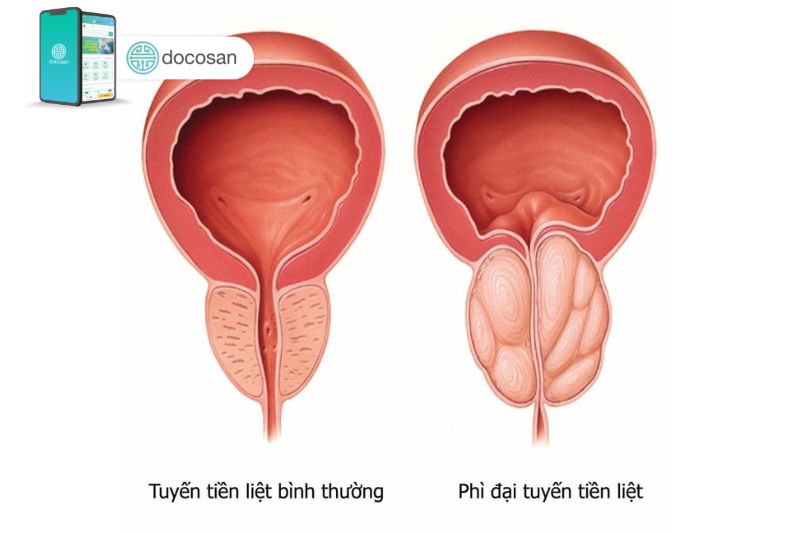

U phì đại tiền liệt tuyến là một bệnh lý nam khoa phổ biến ở người đàn ông trung niên hoặc lớn tuổi. Bệnh còn được gọi là u phì đại lành tính tuyến tiền liệt và có thể gây ra các triệu chứng tiết niệu khó chịu khi kích thước u quá lớn. Nếu người bệnh không được điều trị, u phì đại tiền liệt tuyến có thể gây tắc nghẽn đến hoàn toàn dòng nước tiểu của niệu đạo và từ đó gây vấn đề cho bàng quang, tiết niệu và cả thận.

Tiền liệt tuyến là cơ quan sinh dục của nam giới có vai trò sản xuất hầu hết các chất có trong tinh dịch, từ đó làm chất dịch màu trắng sữa nuôi dưỡng và vận chuyển tinh trùng khi xuất tinh. Vị trí nằm bên dưới bàng quang và tiếp xúc trực tiếp với ống vận chuyển nước tiểu từ bàng quang sẽ đi qua trung tâm của tiền liệt tuyến.

Hầu hết nam giới sẽ được tiếp tục tăng trưởng tiền liệt tuyến trong suốt cuộc đời và sự tăng trưởng này trực tiếp gây ra u phì đại tiền liệt tuyến. Nếu kích thước u đủ lớn và gây chèn ép sẽ gây ra các triệu chứng tiết niệu do gây tắc nghẽn đáng kể lưu lượng nước tiểu. Các bác sĩ nam khoa không chắc chắn chính xác nguyên nhân làm cho tiền liệt tuyến ngày càng to ra, có thể là do những biến đổi sự cân bằng của hormone sinh dục nam của người lớn tuổi.